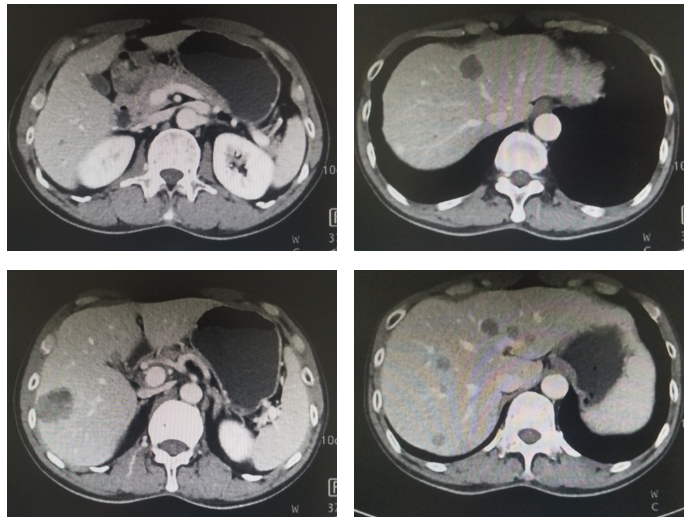

治疗:现给与卡培他滨+曲妥珠单抗+PD-1单抗维持治疗3周期,末次复查CT见图4,血肿瘤标志物AFP水平变化(图5)。

图5. 腹部CT平扫+强化(治疗后7月,2020年5月)

该患者为中年男性,首诊考虑AFP和HER-2双阳性的晚期胃癌合并多发肝转移,无根治性手术及转化治疗机会,晚期一线给与XELOX+曲妥珠单抗+PD-1单抗治疗7周期,期间复查CT确认PR,提示治疗有效,因奥沙利铂不良反应改为卡培他滨联合PD-1单抗维持治疗,治疗过程中肿瘤持续缩小,起病时异常增高的血肿瘤标志物AFP明显下降,目前继续维持治疗中。